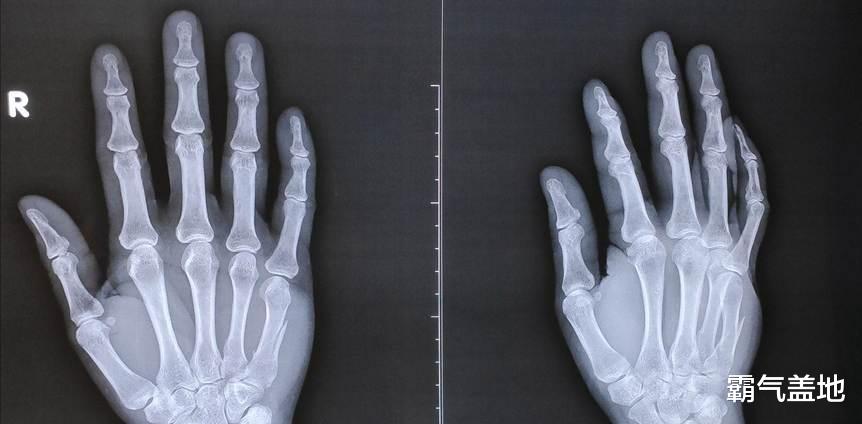

最简单的方法,就是摸摸孩子的手指。 如果你发现孩子的手指骨骼摸起来完全“硬邦邦”的,关节附近也摸不到软骨的那种感觉,那可就要注意了,这很可能暗示着骨骺线即将闭合。或者,你可以观察孩子手指的长度,如果好几年都没有明显变化,也要警惕起来。

还有一些其他的“小前兆”也值得关注。 比如说,孩子的生长速度突然慢了下来,以前一年能长个5-10厘米,现在一年只能长个1-2厘米。 再比如,孩子的第二性征发育加速,女孩乳房开始发育,月经初潮;男孩喉结变大,声音开始低沉。 另外,孩子的脚丫子也可能不再“长大”,鞋码趋于稳定。 如果条件允许,可以带孩子去医院做个骨龄检测,看看骨龄是不是比实际年龄超前了。